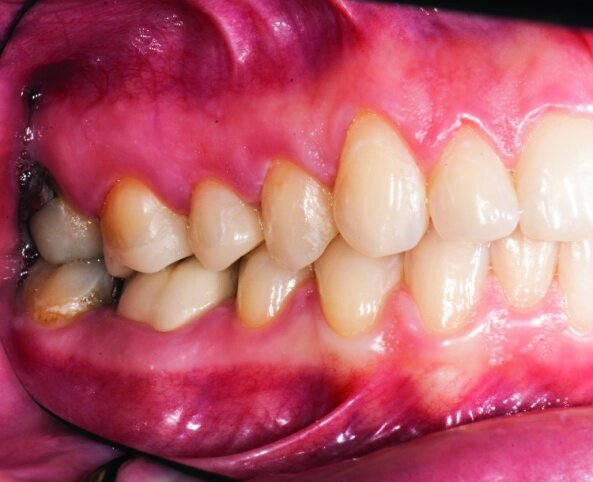

After gross occlusal reduction was completed, the remaining enamel ring was measured (Figs. 9a, b). The enamel rings were noted to be 1.5 mm, and the teeth were prepared for adhesively retained restorations. If the enamel rings were less than 1 mm, the teeth would have been prepared on the axial walls to create retention for cohesively retained crowns.

The remainder of the existing composite resin in #3 and the amalgam in #4 were removed. The occlusal surfaces of the preparations were blended into the interproximal areas using a KS2 bur to create smooth preparations (Figs. 10–15c). There was no retention or resistance form prepared to retain the restorations.

The final result was minimally invasive restorations that appear and function naturally, while decreasing risk of tooth fracture, and minimize further risk to the teeth. (Figs. 35a–36b).